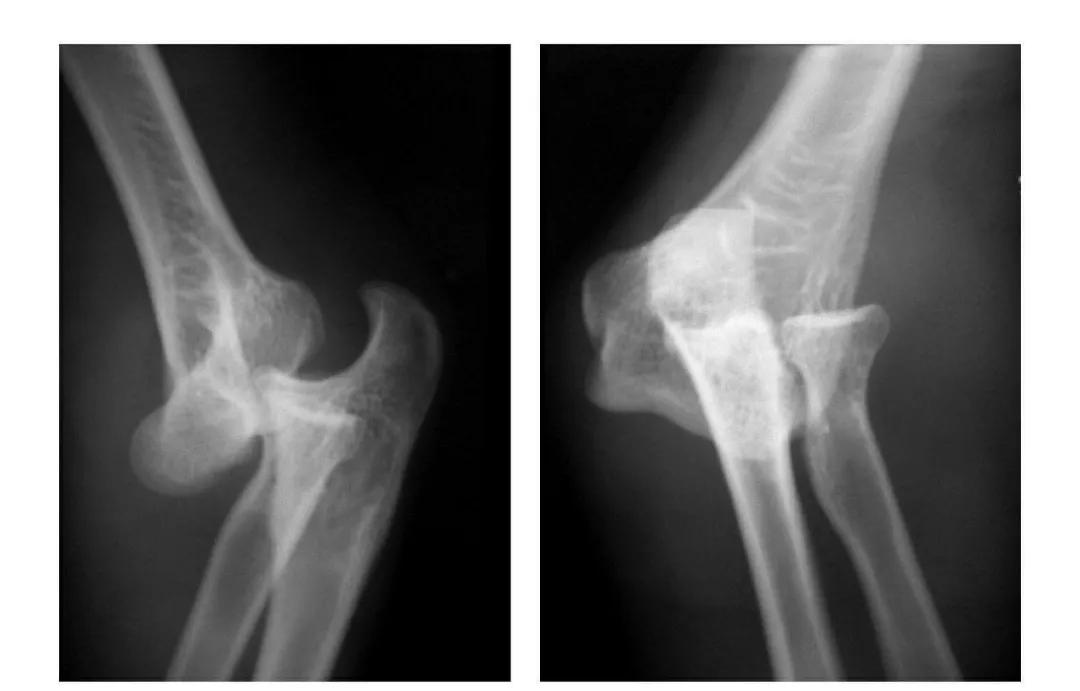

肱骨小头矢状面骨折

本病文献未见报道,即肱骨小头中部呈前后(矢状面)纵向骨折,将小头分为内外两部分。

本病因有明显的外伤史,即健侧小头正常,从而排除了先天因素。

例:肱骨小头矢状面骨折,折线波及外髁皮质骨折片,并鹰嘴突无移位骨折。